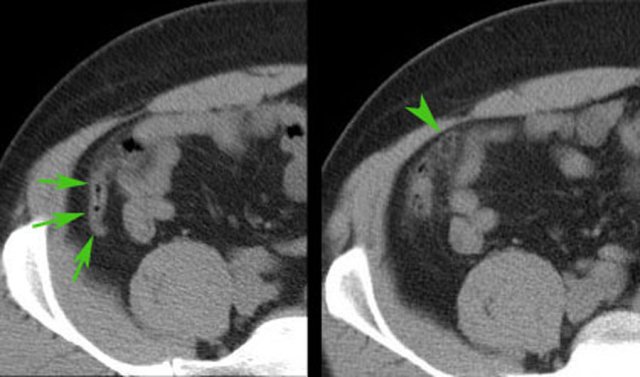

In this 16 year old patient with RLQ pain, enlarged mesenteric lymph nodes surrounded by some inflamed fat (*) were the only US finding and the appendix could not be identified.

CT confirmed the enlarged nodes (arrowheads), but revealed an inflamed appendix (arrow), originating from the cecum in deep pelvic position.

Young patients with acute appendicitis often have secondarily enlarged mesenteric lymph nodes.

In this patient young patient with cecal diverticulitis the most prominent fat stranding (arrowheads) is found around a cecal diverticulum, containing a fecolith (*).

The appendix (arrow) is secondarily inflamed due to the nearby cecal diverticulitis.

Complete cure with conservative treatment.